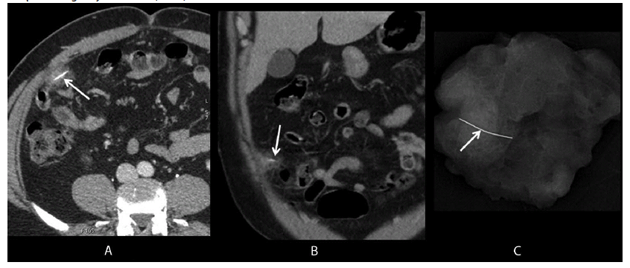

FIGURE. Axial and coronal images (A, B) from intravenous contrast-enhanced computed tomography show a wire grill-cleaning brush bristle in the omentum (arrows), surrounded by soft tissue stranding (inflammation); a specimen radiograph (C) from omental resection confirms complete foreign object retrieval (arrow).

Alternate Text: The figure above consists of three images. The first two are axial and coronal images from intravenous contrast-enhanced computed tomography showing a wire grill-cleaning brush bristle in the omentum, surrounded by soft tissue stranding (inflammation). The third image is a specimen radiograph from omental resection that confirms complete foreign object removal.